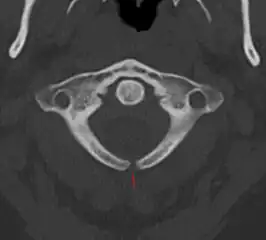

X-ray computed tomography scan of unfused arch at C1